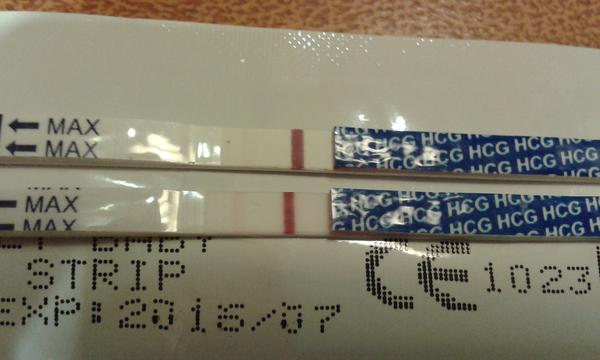

Duch na teste

ahojte babule, mam taku otazku...mate skusenost ze pocas 3 dni vam nesilnela druha ciarka na teste ale bola rovnaka???ako duch????

@claude12345 to nieje pravda sytost ciarky zavisi od stupajuceho hcg v moci a to je u kazdej zeny ine ...ja ti sem pridam moje testiky prvy robeny den po vynechani ms a druhy ked mi ms meskala 3 dni...a teraz mi v izbicke spinka nase zlaticko pomalicky bude mat pol roka tak neboj si tehu budes maminka

@claude12345 neboj sa vsetko dobre dopadne mas krasny testik cize hcg stupa pomalicky a teraz uz iba ostat v klude nech drobciatko krasne rastie a ani sa nenazdas a tiez budes mat v postielke nadherne babatko drzim ti moc palceky

@claude12345 tak ja vidím ružovú druhu čiarku a kanáliky zvyknú byt sivé alebo biele ryhy 😉

@karmela na fotke tu ružovu vidieť slabšie no naživo je o troška silnejšia .. Dakujem že si mi povedala akej farby su kanaliky ..takže možnosť tam je že som tehu ..🙂 len to čakanie do pondelka aby to potvrdil ..🙂

@claude12345 tak ja ju vidím ružovú aj na foto je to na dobrej tehu ceste 😉Správ testik este v nedeľu a uvidis bude silnejšia čiarka zase podľa mna 😉

@claude12345 no tak ked ti vyšiel večer takýto ráno bude isto silnejší 😉Trochu stmavené foto

@karmela tak na tej stmavenej fotke vidim už aj tu čiarku hrubšiu tak tomu začínam veriť už viac 🙂 takže v nedelu rano si robim testík 🙂

@claude12345 ja som mala taku slabucku ciarku presne pred rokom po 4 dnoch od ocakavanej ms a po 9 bola silnejsia ale este stale nebola ako kontrolna. teraz mi ta ciarocka spinka v postielke. drzim palce, budes maminou 😉